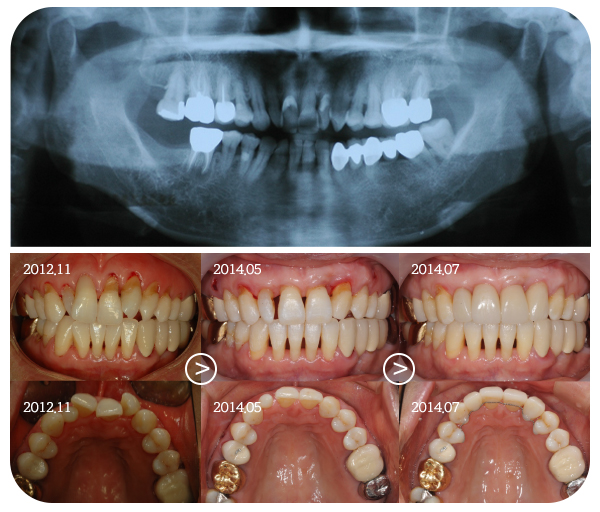

Before & After

> 토브 일반진료 사례

> 토브 협진치료 사례

case 01

교정+보철+치은이식

case 02

교정+임플란트